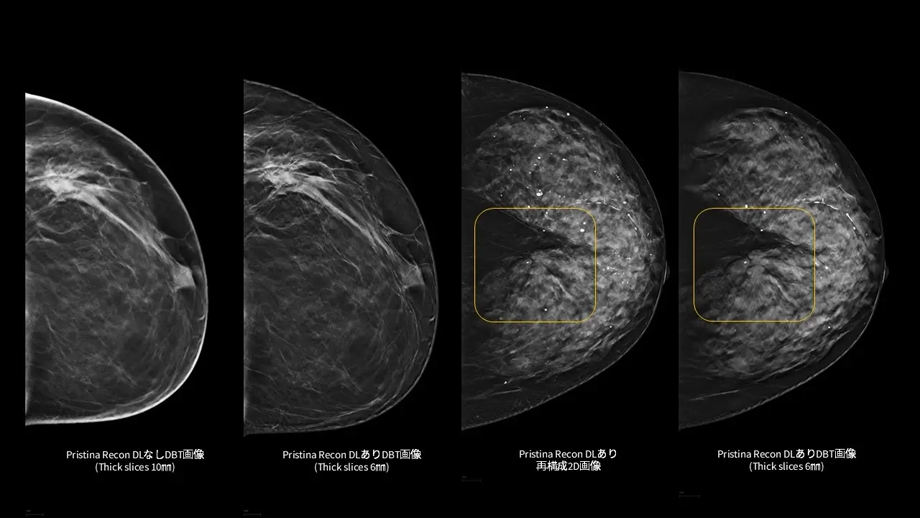

「Pristina Recon DL」¹は、MRIの画像再構成にディープラーニングを適用したGEヘルスケア独自のAIR™ Recon DL技術を基盤としている。本アプリケーションで、乳房のデジタルブレストトモシンセシス (DBT/3Dマンモグラフィ) 技術の更なる可能性を追求し、低線量での撮影でも、より高画質な画像の提供を目指する。また、アーチファクト(虚像)や視覚的ノイズの低減を図り、微細構造の視認性の向上にも寄与する。²,³

「Pristina Recon DL」は、ディープラーニングと逐次近似再構成技術を活用した、デジタルブレストトモシンセシス(DBT/3Dマンモグラフィ)向けの画像再構成技術である。また、被ばく線量を増加させることなく、高画質で安定したDBT/3Dマンモグラフィ画像の提供を目指す。

さらに、ディープラーニングを用いた高度な画像再構成技術により、アーチファクト(虚像)や視覚的ノイズを低減し、微細構造の視認性を向上させる。これにより、DBT/3Dマンモグラフィおよび再構成2D画像の双方において、読影に必要な情報をより明確に可視化し、診断を支援する読影環境の向上に貢献する。